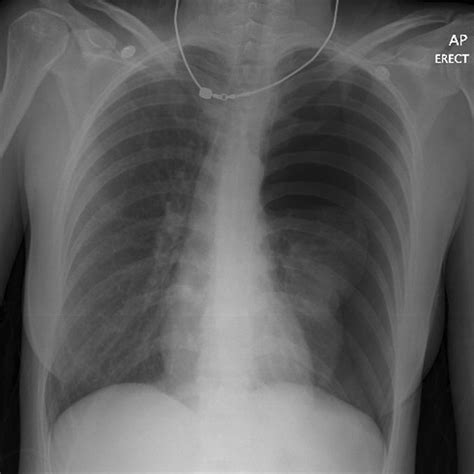

Chest X-rays are the primary imaging modality used to diagnose pneumothorax. They provide a clear view of the lungs and pleural space, allowing radiologists to identify the presence of air. The key features to look for in a pneumothorax in X-ray include:

There are different types of pneumothorax, each with its own characteristics on an X-ray:

• pneumothorax x ray vs normal